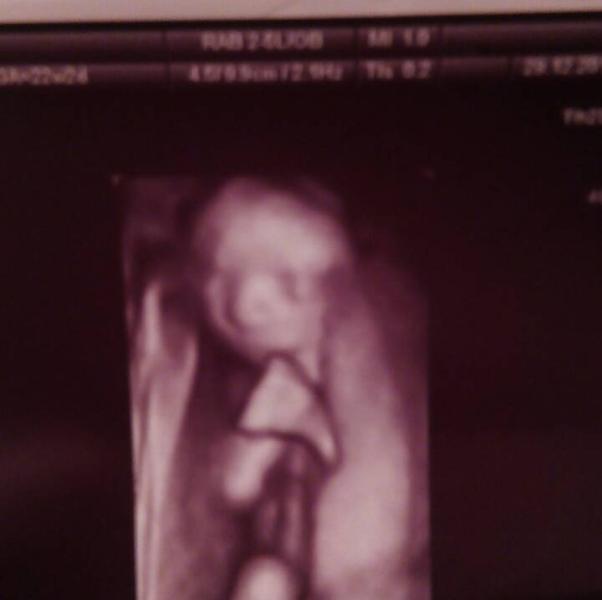

девочки, делали перед Новым Годом узи 😊 Всё просто замечательно ) правда выяснилось,что мальчик у нас, а не девочка как мы думали ) были с мужем и мамой моей ) она сказала,нос что-то большой и малыш тут же спрятал его ручкой и отвернулся 😀 но вот со вчерашнего дня мне не дает покоя это ( правда чтоль большой? или это ещё поменяться может или на узи на этом сроке ещё не сильно видно? что-то мне подруга вчера сказала у них сразу маленький был и я переживать начала из головы никак не выходит 😔

Не загоняйтесь ))) Нормальный нос. К тому же, пропорции лица будут меняться. Может даже такое быть, что ребёночек родится с "большим" носом, а потом лицо будет увеличиваться быстрее, чем нос, который уже не будет казаться большим. Так что, по поводу носа сейчас уж точно не надо переживать

Нос к 12 годам формируется, поэтому не переживай! Я недавно сравнила фото УЗИ и реального. Тоже на УЗИ носик большеват :) а в жизни хорошенький

Ну какой же он большой!🙈😅 перестаньте накручивать себя! Аккуратненький носик)